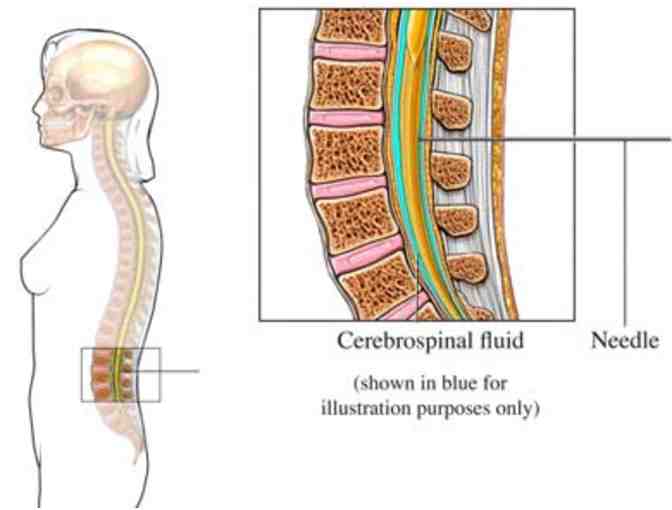

[Wikipedia, 6/18/13] a form of bodywork or alternative therapy focused primarily on the concept of "primary respiration" and regulating the flow of cerebrospinal fluid by using therapeutic touch to manipulate the synarthrodial joints of the cranium.